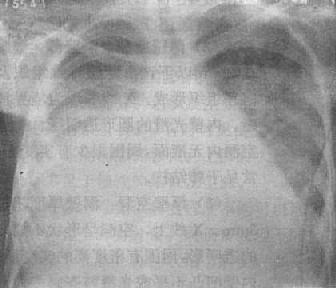

原发病灶及病灶周围炎X线表现为边界模糊的云絮状影,可大可小,大者可占据数个肺段甚至一个肺叶,婴幼儿以大叶型及肺段型多见。自原发病灶引向肺门的淋巴管炎可表现为数条索条状致密影,当病灶周围炎范围较大时则淋巴管炎及淋巴结炎可被掩盖而不能显示。肺门与纵隔增大的淋巴结表现为肿块影(图3-1-20)。原发病灶周围炎范围较小时,可以出现原发病灶-淋巴管炎-淋巴结炎三者组成的哑铃状双极现象。但此种典型征象并不多见。原发病灶周围炎范围较大时可误为大叶性肺炎,结合临床症状及肺门淋巴结增大可以鉴别。

图3-1-20 原发综合征

右侧下肺野靠近心右缘可见边缘模糊的云絮状影,

范围较大,肺门淋巴结增大,边界不清